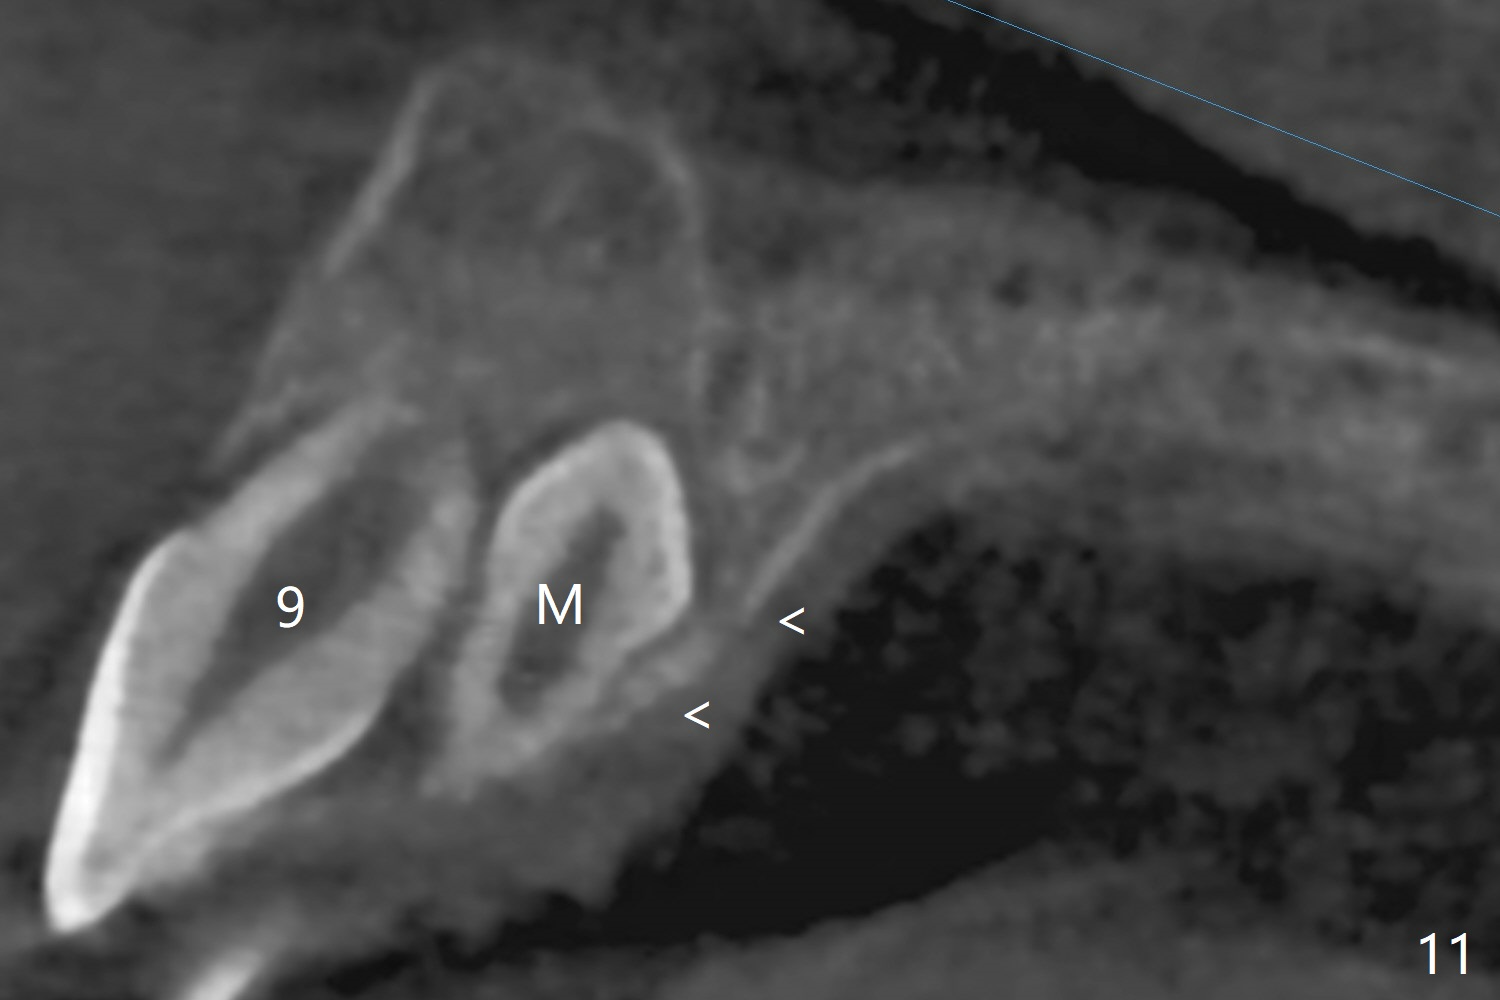

The father of a 7-year-old boy wonders why the upper central incisors, particularly #9, are off (Fig.1 3-D CT tooth coloring). Fig.2 (bone coloring) does not reveal much. Fig.3 (MIP, more transparent) reveals a supernumerary tooth, called mesiodens (M, an extra central incisor, abnormally shaped (cone), near the midline). Palatal view shows that the mesiodens points to the midline and distal (arrow). A palatal gingival sulcus incision will be made to expose the extra tooth (Fig.5). An elevator will be used as midline and distal as possible to avoid damage to the root of #9 and the tooth bud of #10 (Fig.6 MIP). Photos will be taken frontally and palatally preop and after incision and exposure of the mesiodens (palatal).

There is a large diastema between the upper central incisors (Fig.7). The left anterior palate is slightly elevated (Fig.8 *). In fact the cortex overlying the mesiodens (Fig. 9 *, 11 <) is to be removed with a surgical handpiece in order to extract the mesiodens (Fig.10). The left central shifts mesial in 7.5 months postop, whereas the right one remains in place (Fig.12). The tooth #7 is unerupted 1 year 4 months postop (Fig.13).